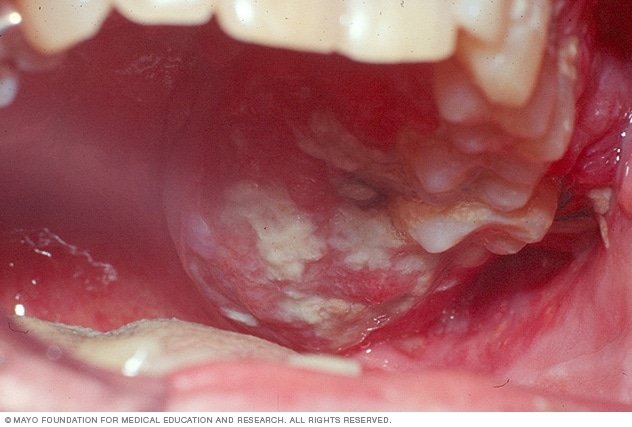

Oral Ulcers

One of the earliest and most common signs of mouth cancer is the presence of persistent oral ulcers. These ulcers may be painful, slow to heal, and often have a raised, irregular edge. They can occur anywhere in the oral cavity, including the lips, tongue, and inside the cheeks.

Lump or Thickening

The development of a lump or thickening in the oral cavity or neck area should not be ignored. These abnormal growths may be painless but gradually increase in size over time.